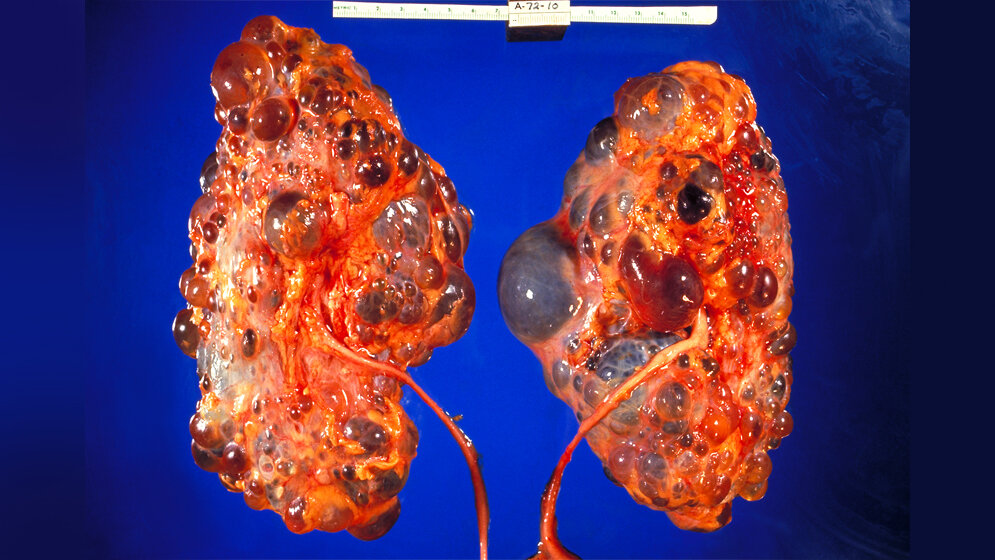

Autosomal dominante polyzystische Nierenerkrankung ADPKD

Etwa jede tausendste Person leidet an der autosomal dominanten polyzystischen Nierenerkrankung ADPKD, die wiederum in ca. 50 % der Fälle ab Mitte des fünften Lebensjahrzehnts in einen unwiederbringlichen Verlust der Nierenfunktion mündet. Dies bedeutet für die Patientinnen und Patienten lebenslange Hämodialyse oder Nierentransplantation und eine Verkürzung der Lebenserwartung. Zudem leiden die Betroffenen durch ihre Nierenerkrankung an Bluthochdruck, Schmerzen und Infektionen. Seit längerer Zeit ist bekannt, dass das kontinuierliche Zystenwachstum maßgeblich zu all diesen Problemen führt. Die bisherigen therapeutischen Möglichkeiten sind nur sehr eingeschränkt wirksam und von relevanten Nebenwirkungen begleitet.